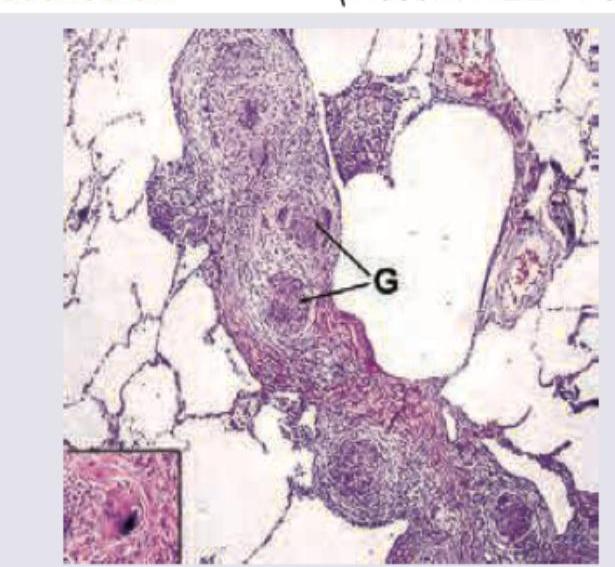

'Masson Bodies' formed due to proliferation of immature collagen are a characteristic histopathological finding seen in which of the following conditions?

Explanation: ***Cryptogenic Organizing Pneumonia*** - **Masson bodies**, which are intraluminal plugs of organizing connective tissue composed of fibroblasts, myofibroblasts, and immature collagen, are the **hallmark histopathological feature** of cryptogenic organizing pneumonia (COP) [1]. - These plugs are found predominantly in the **alveolar ducts** and **bronchioles**, leading to a characteristic pattern of organizing pneumonia [1]. *Lymphocytic Interstitial Pneumonia* - Characterized by a **dense interstitial infiltrate** dominated by **lymphocytes**, plasma cells, and histiocytes, often forming germinal centers. - It is frequently associated with **immunodeficiency states** such as HIV infection or autoimmune diseases like Sjögren's syndrome. *Desquamative Interstitial Pneumonia* - Marked by the accumulation of a large number of **macrophages** within the alveolar spaces, with minimal interstitial inflammation or fibrosis. - Primarily seen in **smokers** and is thought to be a reaction to inhaled particulate matter. *Respiratory Bronchiolitis* - Characterized by **peribronchiolar inflammation** and fibrosis, with pigment-laden macrophages accumulating within the respiratory bronchioles. - This condition is also strongly associated with **cigarette smoking** and is considered a milder variant of interstitial lung disease. **References:** [1] Cross SS. Underwood's Pathology: A Clinical Approach. 6th ed. Common Clinical Problems From Respiratory Tract Disease, pp. 330-331.